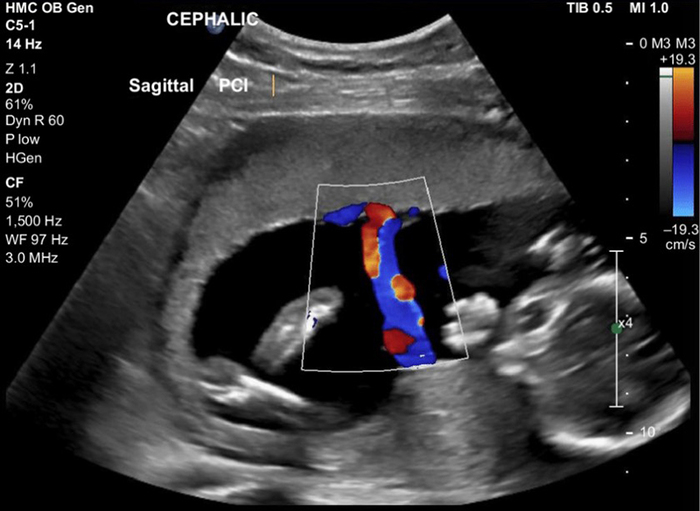

Siêu âm Doppler màu (Color Doppler)

Doppler màu là sự kết hợp giữa siêu âm xám (B-mode) và Doppler, cho phép hiển thị hình ảnh dòng chảy máu dưới dạng màu sắc trên màn hình. Dòng máu chảy về phía đầu dò thường hiển thị màu đỏ, còn dòng chảy đi xa hiển thị màu xanh. Kỹ thuật này giúp bác sĩ quan sát trực quan hướng và tốc độ dòng máu, phát hiện nhanh bất thường trong mạch máu hoặc tim. Doppler màu thường được dùng rộng rãi trong tim mạch, sản khoa và mạch máu ngoại vi.

Trong sản khoa, Doppler thai được sử dụng để theo dõi dòng máu trong động mạch rốn, động mạch não giữa và các mạch máu khác của thai nhi nhằm đánh giá tình trạng trao đổi oxy và dinh dưỡng giữa mẹ và con. Phương pháp này giúp phát hiện các tình trạng nguy hiểm như suy thai, thiểu ối, tăng huyết áp thai kỳ hoặc rối loạn tăng trưởng trong tử cung. Đây là kỹ thuật quan trọng trong quản lý thai kỳ nguy cơ cao.

Trong sản khoa, siêu âm Doppler thường được chỉ định ở giai đoạn giữa và cuối thai kỳ (từ tuần 20 trở đi), đặc biệt khi có dấu hiệu thai phát triển chậm, mẹ bị tăng huyết áp thai kỳ, tiền sản giật, hoặc có nguy cơ suy thai. Kỹ thuật này giúp đánh giá lưu lượng máu giữa mẹ và thai nhi, từ đó xác định nguy cơ thiếu oxy, kém phát triển hoặc tử vong thai trong tử cung. Ngoài ra, siêu âm Doppler còn được sử dụng trong phụ khoa để phân biệt u lành hay ác tính dựa trên mức độ tưới máu của khối u, cũng như trong chẩn đoán bệnh lý thần kinh khi cần khảo sát dòng máu trong não (Doppler xuyên sọ). Tùy theo từng mục đích, bác sĩ sẽ chỉ định loại Doppler phù hợp để đảm bảo chẩn đoán chính xác và can thiệp kịp thời.